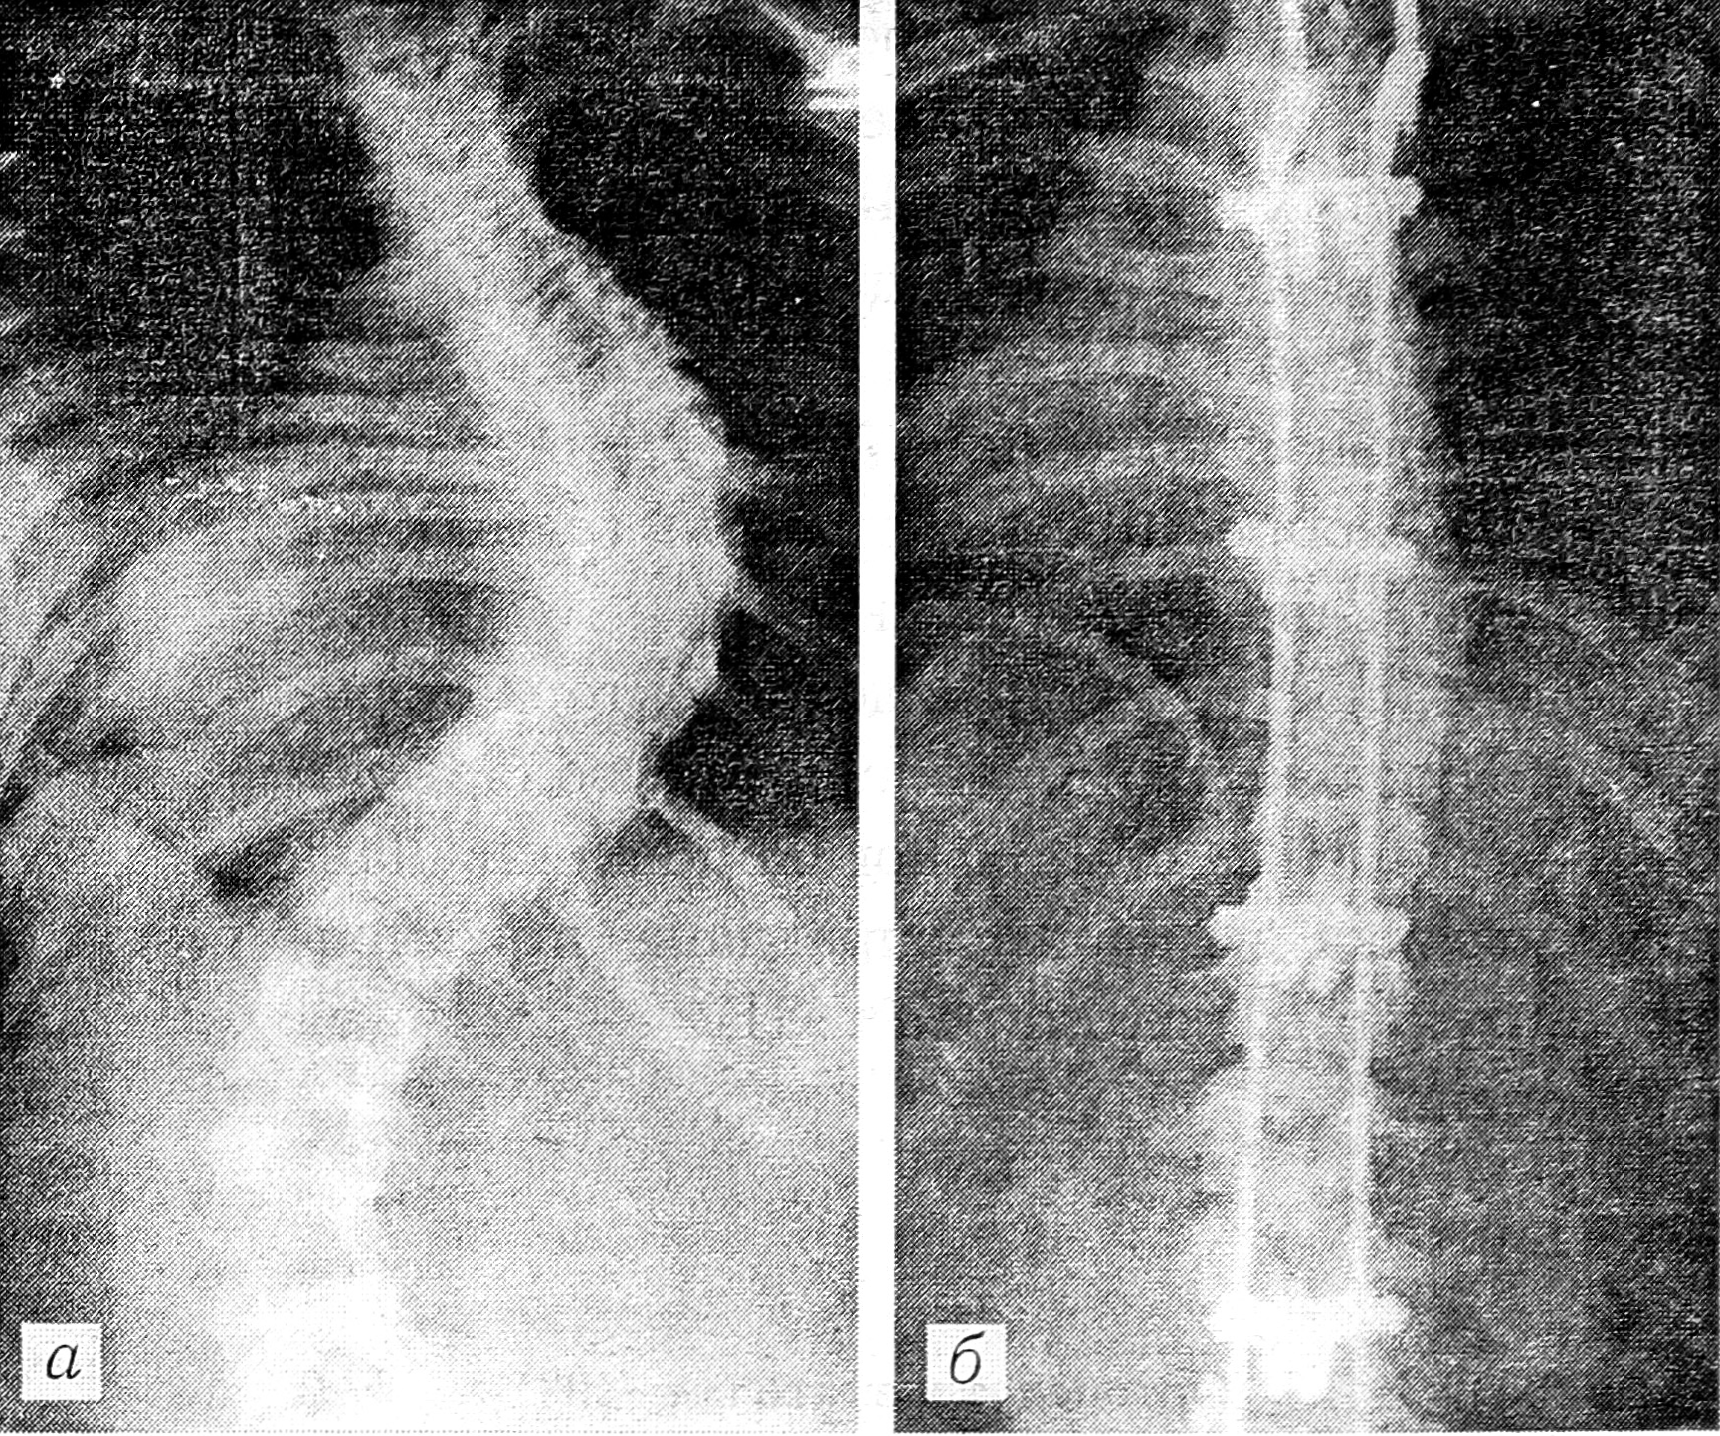

Рис. 1. Спондилограммы больной К. 13 лет.

a — до операции: искривление 67° по Коббу; б — после операции: остаточная кривизна 23°, коррекция 66%. Девочка встала с постели на 10- е сутки, дополнительная внешняя иммобилизация не использовалась.